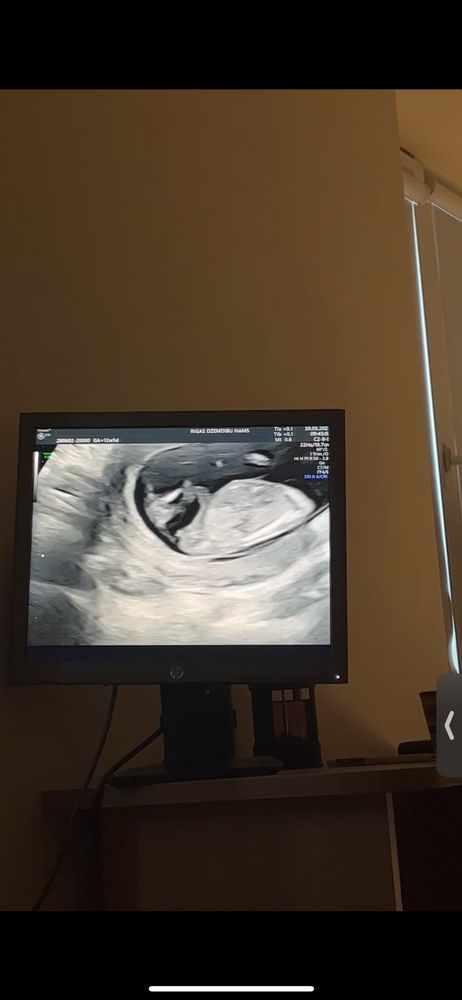

Вчера была на первый скрининг в 12,5 недель. Сказали что пол можно узнать только через 2 месяца. В видео потом увидела этот бугорок, подумала что это яица, но почитала в интернете что это бугорок и можно как то определить будит мальчик или девочка, так вот, что думаете? И кстати у нас сердцебиение 159, читала что у мальчиков обычно ниже. 🤔 Очень хочу девочку😄🥰

Похоже на девочку ,но там ножки видно и пол Богорок вроде параллельно ,но конечно достовернее через месяц